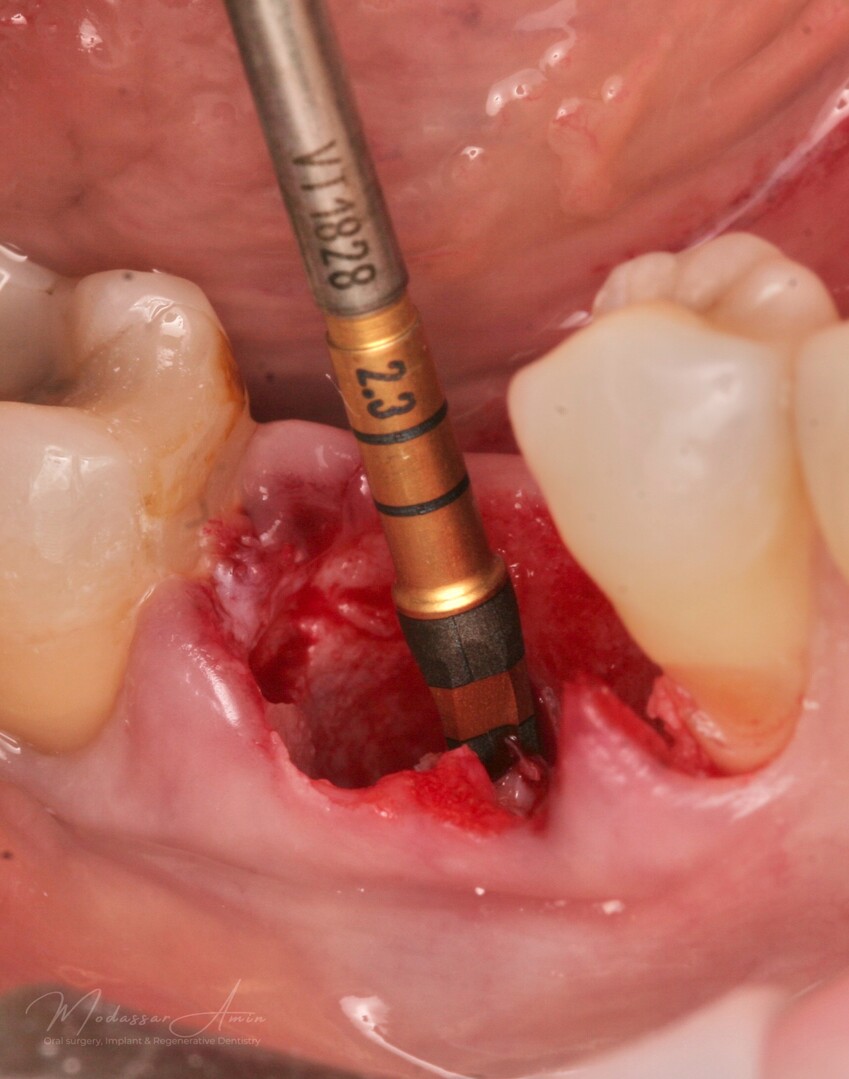

PATIENTFALL

"Pasienten presenterte med tann 46 som ikke kunne bevares grunnet en dyptgående infraksjon inn i furkasjonen. Forholdene lå til rette for en immediate implantatbehandling. Ved hjelp av Versah osseodensifikasjonsbor ble det interradikulære beinet ekspandert på en skånsom og forutsigbar måte, noe som ga høy primærstabilitet (>40 Ncm) til tross for en lokal bendefekt apikalt mesialt etter kronisk apikal periodontitt. Den gode stabiliteten muliggjorde bruk av SSA (Sealing Socket Abutment) for forsegling. På grunn av tynn bløtvevsfenotype bukkalt ble behandlingen supplert med bindevevstransplantat (CTG)"

Versah borr 2.3